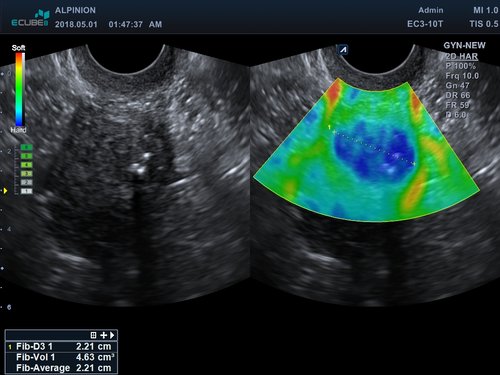

• EC3-10T (3-10 MHz) für Ultraschalluntersuchungen in Bereichen Geburtshilfe, Gynäkologie, fetales Echo, Urologie

• Farbdoppler: farbige Darstellung der Richtung des Blutflusses

• Powerdoppler: sensitive, farbige Darstellung des Blutflusses unabhängig von Geschwindigkeit und Richtung

• DPDI: Technologie, die Sensitivität des Powerdopplers mit der Flussrichtungsinformation des konventionellen Farbdopplers kombiniert